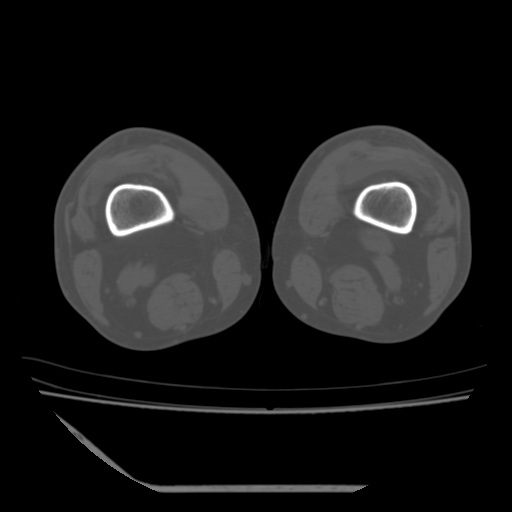

标题: CT13225:老年男性,左膝关节疼痛数月;请各位老师讨论。 [打印本页]

标题: CT13225:老年男性,左膝关节疼痛数月;请各位老师讨论。

骨质增生,骨性关节面硬化,关节积液,考虑退行性骨关节病

关节腔内少量积液,关节面退变。

双膝退变

骨质增生,骨性关节面硬化,关节间隙失常,关节积液,考虑退行性骨关节病.

这个病例诊断:退行性骨关节炎